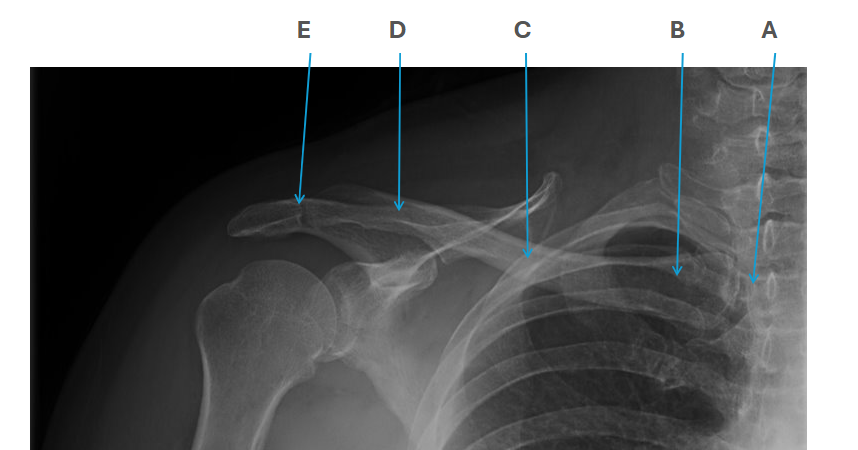

what is clavicle A

SC joint

what is clavicle B

sternal end

what is clavicle C

shaft/body

what is clavicle D

acromion

what is clavicle E

AC joint

what is this an x-ray of?

acromioclavicular dislocation